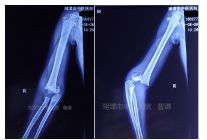

入院拍片如下:

四步复位法整复后拍片复查